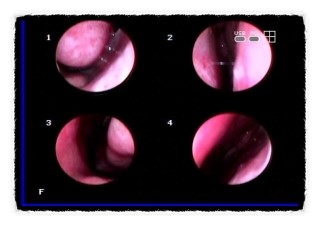

그다음에 애초에 입구가 폐쇄되거나 생활을 할 수 없을 정도로 증상이 심하다면 내시경을 이용해서 수술을 하셔야 합니다.보통 한쪽 콧구멍 당 30분 안에 끝나는데요.수술을 받은 후에는 꾸준한 관리에 신경을 써야 합니다.